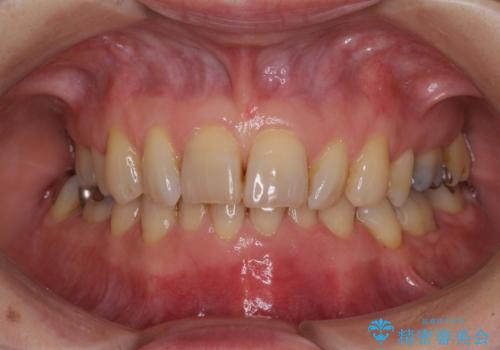

- 下顎前歯が痛んで近医を受診したところ、下顎前歯2本を抜歯してインプラント治療が必要と診断されたとのことで来院された患者様です。

診査の結果、下顎左側中切歯の神経が失活していることが痛みの原因であり、根管治療を行う必要があると診断されました。

根管治療を行った後にオールセラミッククラウンにて補綴することとしました。

隣在歯にも根尖部の炎症が及んでいるように見えましたが、術前診査では神経が失活している様子がなかったため、まずは原因歯から処置を行うこととしました。

初回の根管治療後には痛みが速やかに改善し、6か月後のレントゲン写真では根尖の病変が消失していることが確認できました。